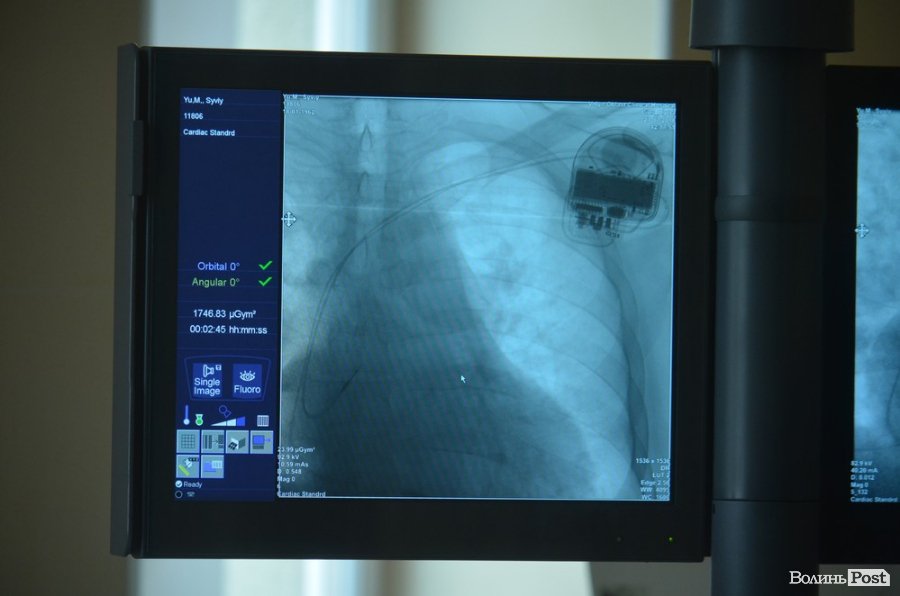

У ході операції двокамерний кардіовертер вживлюють у лівій підключичній області, його розміщують на грудному м’язі. Лікар виконує розріз, формує кишеню та через ліву підключичну вену заводить до серця два електроди. Один фіксують у порожнині правого шлуночка, інший – у вушку правого пересердя. Шлуночковий електрод є шоковим і саме він дозволяє наносити розряд. Передсердний електрод використовують для стимуляції передсердь та стимуляції електронної активності.